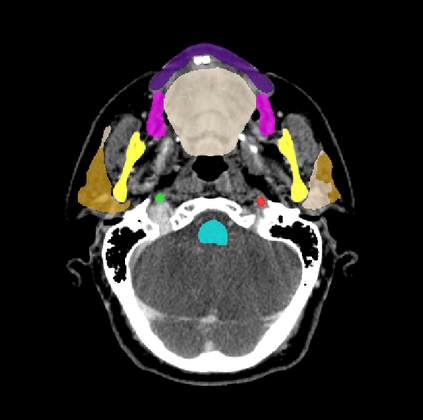

Organ at risk (OAR) segmentation is a critical process in radiotherapy treatment planning such as head and neck tumors. Nevertheless, in clinical practice, radiation oncologists predominantly perform OAR segmentations manually on CT scans. This manual process is highly time-consuming and expensive, limiting the number of patients who can receive timely radiotherapy. Additionally, CT scans offer lower soft-tissue contrast compared to MRI. Despite MRI providing superior soft-tissue visualization, its time-consuming nature makes it infeasible for real-time treatment planning. To address these challenges, we propose a method called SegReg, which utilizes Elastic Symmetric Normalization for registering MRI to perform OAR segmentation. SegReg outperforms the CT-only baseline by 16.78% in mDSC and 18.77% in mIoU, showing that it effectively combines the geometric accuracy of CT with the superior soft-tissue contrast of MRI, making accurate automated OAR segmentation for clinical practice become possible. See project website https://steve-zeyu-zhang.github.io/SegReg